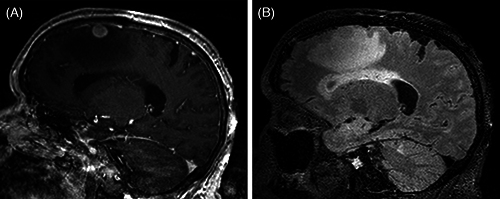

原发性渗出淋巴瘤(PEL)是一种不常见的与人类疱疹病毒 8 相关的 B 细胞淋巴瘤,占所有 HIV 相关淋巴瘤的 3-4%。它传统上表现为胸膜、心包和/或腹腔积液,但偶尔也会表现为无积液的腔外或实性肿块。据报道,原发性渗出淋巴瘤的腔外或实性变异表现在皮肤、胃肠道、肺部和淋巴结。然而,中枢神经系统淋巴瘤的病例却鲜有报道。我们描述了一例表现为脑部肿块的原发性腔外或实性变异性渗出淋巴瘤(HIV 阳性男性),重点介绍了这一罕见病例的临床病理和免疫分型结果。

Primary effusion lymphoma (PEL) is an uncommon B-cell lymphoma associated with human herpesvirus 8 and comprises 3-4% of all HIV-related lymphomas. It traditionally presents as a pleural, pericardial, and/or peritoneal effusion, though it can occasionally manifest as an extracavitary or solid mass in the absence of an effusion. The extracavitary or solid variant of primary effusion lymphoma has been reported in the skin, gastrointestinal tract, lung, and lymph nodes. However, very few cases have been reported in the central nervous system. We describe a case of extracavitary or solid variant of primary effusion lymphoma presenting as a brain mass in an HIV-positive man, highlighting the clinicopathologic and immunophenotypic findings of a rare entity.